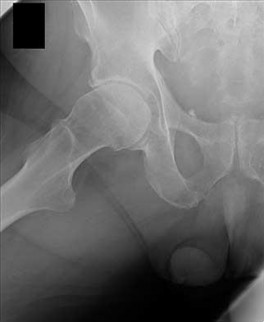

Prophylactic pinning of the contralateral hip in a patient with a Slipped Capital Femoral Epiphysis (SCFE) is most strongly indicated in which of the following scenarios?

Correct Answer: 10-year-old male with hypothyroidism

Prophylactic pinning of the contralateral hip is generally indicated in patients at high risk for bilateral disease. Risk factors for bilateral SCFE include young age at presentation (< 10 years for girls, < 11 years for boys), endocrine disorders (e.g., hypothyroidism, growth hormone deficiency, renal osteodystrophy), and previous radiation therapy. Thus, the 10-year-old male with hypothyroidism represents the highest risk among the choices.